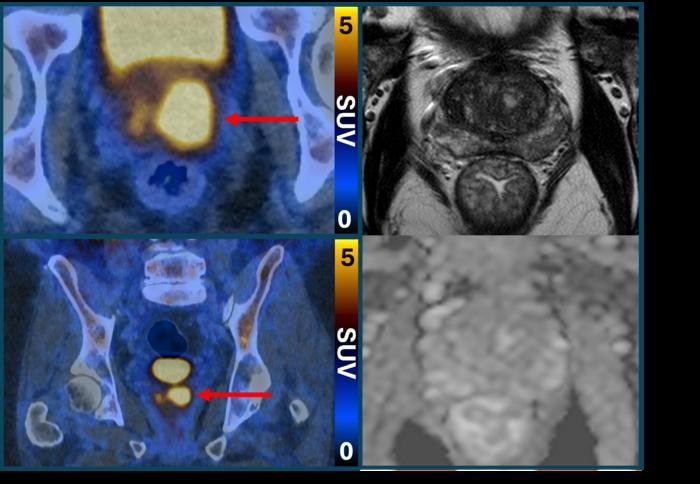

Neue Forschungsergebnisse zeigen, dass ein bildgebender Test die Anzahl der Personen, die nach unklaren oder beruhigenden Ergebnissen einer MRT-Untersuchung eine Biopsie bei Verdacht auf Prostatakrebs benötigen, sicher halbieren könnte Die Ergebnisse der PRIMARY2-Studie werden heute [Freitag, 13. März 2026] auf dem Kongress der Europäischen Gesellschaft für Urologie in London (EAU26) vorgestellt. Die PSMA-PET/CT-Untersuchung identifiziert aggressivere Prostatakrebszellen, die potenziell gefährlich sind und behandelt werden müssen. Sie nutzt dazu ein Molekül, das an die Prostatakrebszellen bindet und diese zum Leuchten bringt, sodass sie im Bild als helle Flecken erscheinen. Laut der Studie könnte dies auch dazu beitragen, das Risiko einer Überdiagnose zu verringern, indem festgestellt wird, welche Tumore ein geringes Risiko darstellen und niemals Schaden anrichten werden. Bei Verdacht auf Prostatakrebs wird üblicherweise eine MRT-Untersuchung durchgeführt, um nach auffälligen Bereichen der Prostata zu suchen. Sind die MRT-Ergebnisse verdächtig oder nicht eindeutig, wird…